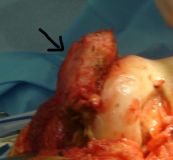

2. Heterotopic ossification on the medial side of the left knee in a 30-year-old man.

Treatment: Surgical removal

I. 3D reconstruction of the knee following CT scan, the heterotopic ossification is obvious following a head injury that happened two years down the line II. During procedure, the black arrow shows the heterotopic ossification III. Anteroposterior x-ray knee after the removal of the heterotopic ossification